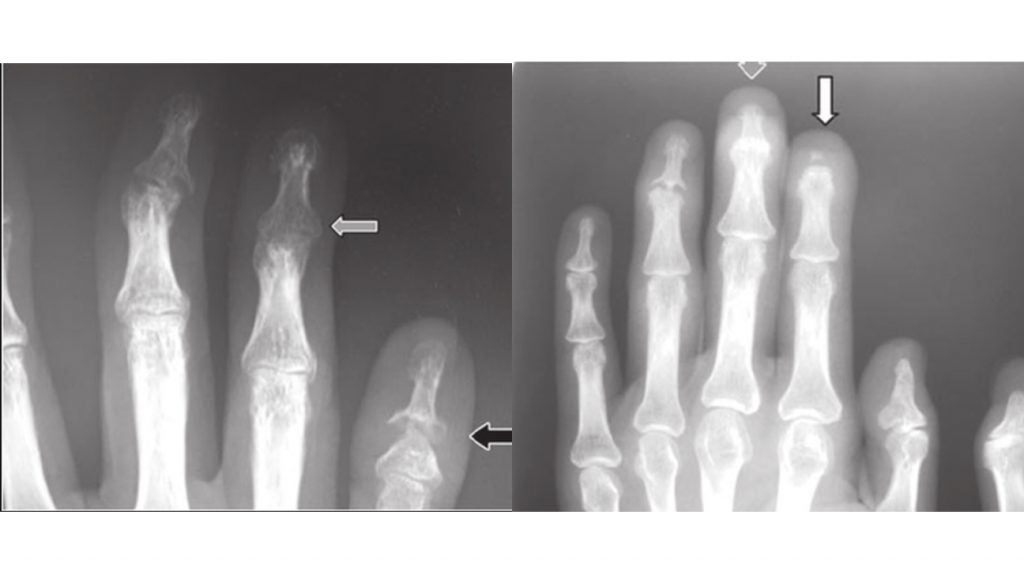

What to know about pencilincup deformity Cups Disease In Humans  There are more than 200 different types of primary cancer. Web cancer of unknown primary (cup) is diagnosed at the metastatic stage. Patients with cups often have a. Web  carcinoma of unknown primary (cup) is a rare disease in which malignant (cancer) cells are found in the. Web  if a cancer has spread but the original tumor can’t be found,. Cups Disease In Humans.